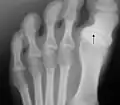

Radiography of the left foot of a young male showing progressive hallux varus